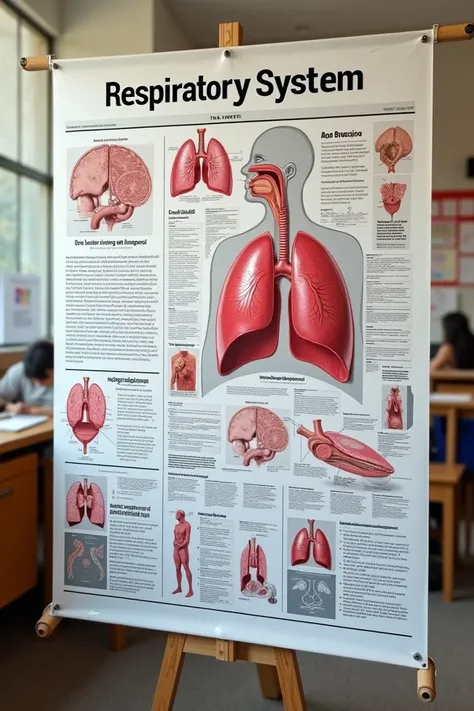

Make a folder about bacterial pneumonia

Make a folder about bacterial pneumonia

Make a folder about bacterial pneumonia